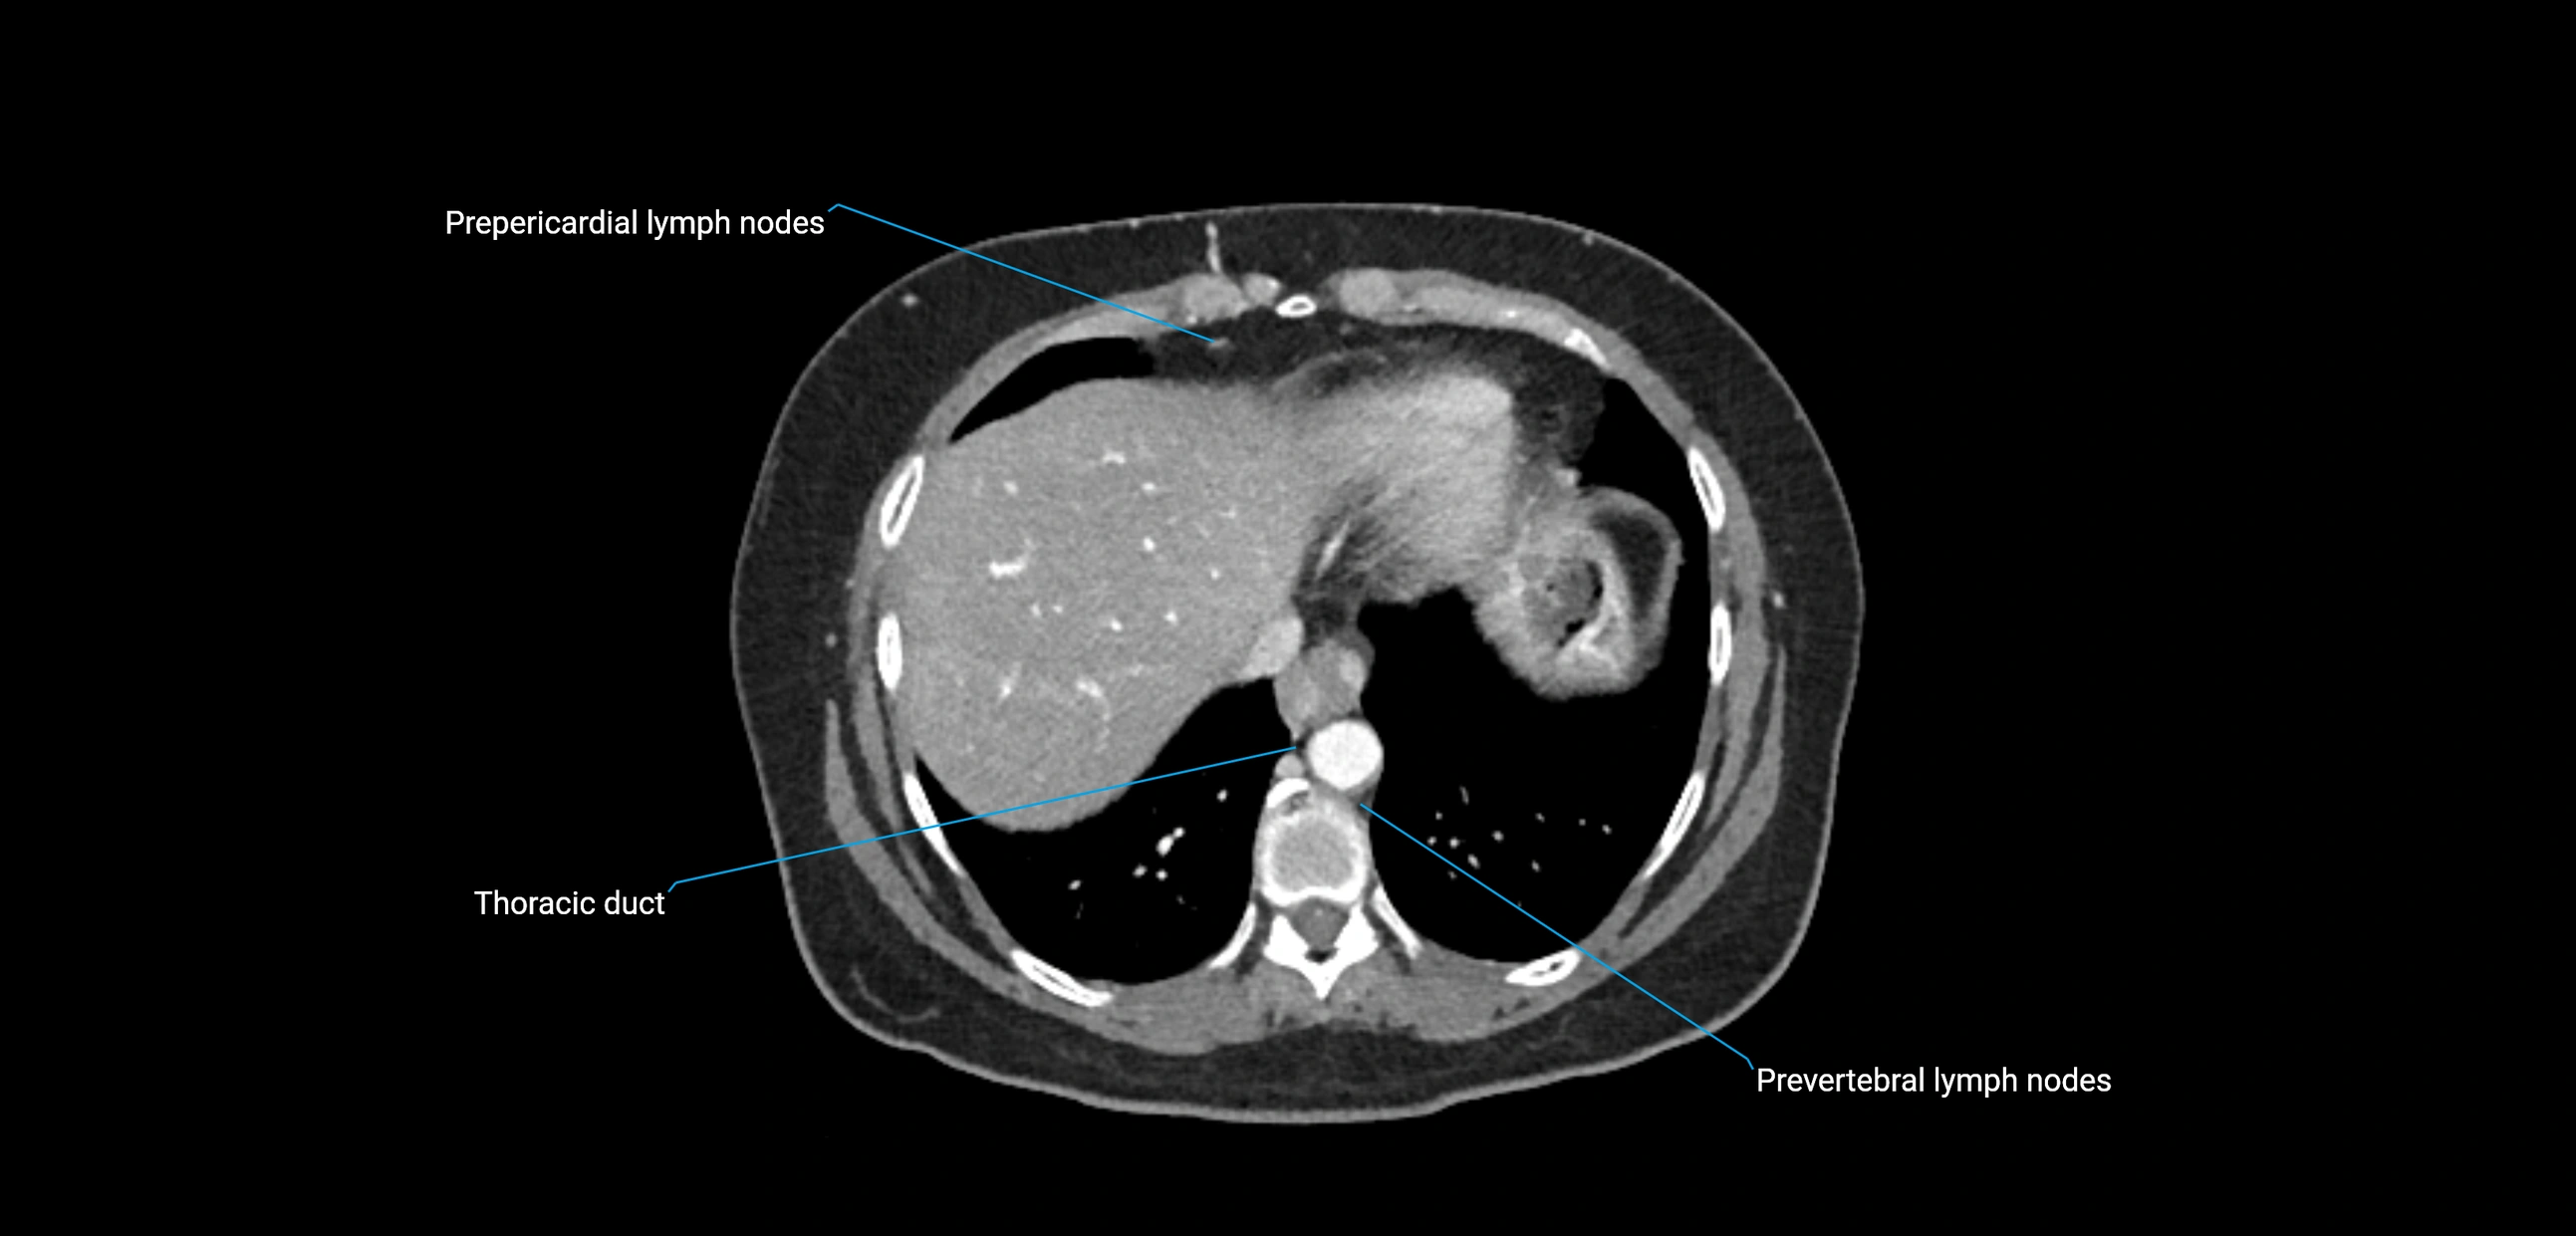

CT Appearance

CT Post-Contrast:

• Normal nodes enhance homogeneously

• Malignant nodes may show heterogeneous enhancement, central necrosis, or conglomerate formation

CT Venography (CTV):

• Demonstrates nodal encasement or compression of adjacent vessels (aorta, IVC, renal veins)

• Useful in staging testicular and ovarian malignancies

• Provides 3D reconstructions for retroperitoneal lymph node dissection planning